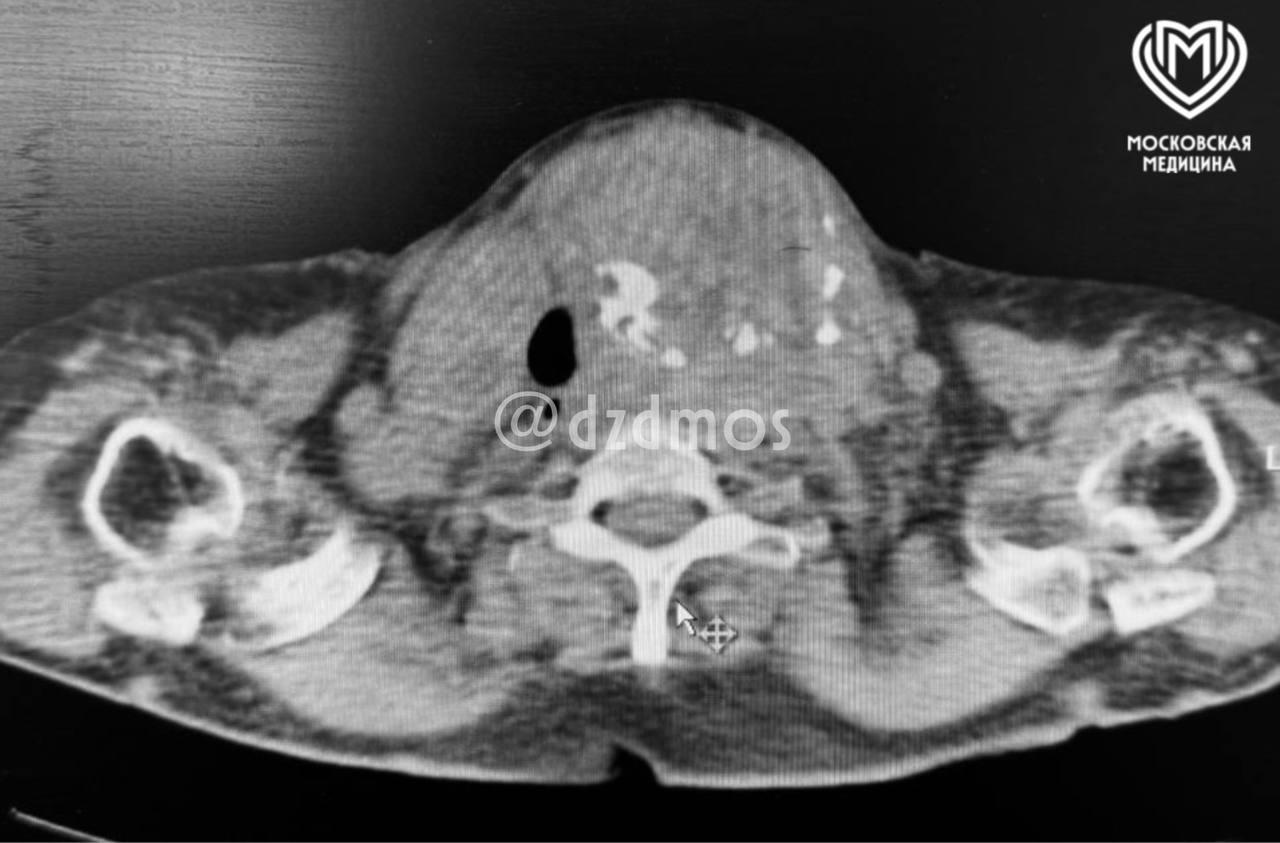

Врачи удалили у пенсионерки гигантский зоб размером с баскетбольный мяч.

79-летняя женщина обратилась к врачам на жалобы с дыханием. Женщину отправили в реанимацию —

огромный зоб, который сильно сжимал трахею, оставляя в ней всего 4 мм свободного

пространства.

В любой момент у женщины могла начаться остановка дыхания. Также врачи нашли у нее проблемы с сердцем и сдавленные сосуды на шее.

«Нам нужно было провести операцию по удалению щитовидной железы в условиях практически невозможной интубации! Наши анестезиологи совместно с эндоскопистами применили уникальную методику: интубацию в сознании с использованием фиброскопа, что позволило аккуратно провести дыхательную трубку через суженный участок трахеи без риска полной закупорки дыхательных путей. Далее хирурги провели операцию менее, чем за 2 часа, через разрез на шее удалив щитовидную железу с многоузловым поражением объемом ~ 900 мл (при норме до 20 мл у здоровых людей)», — пояснили в больнице.